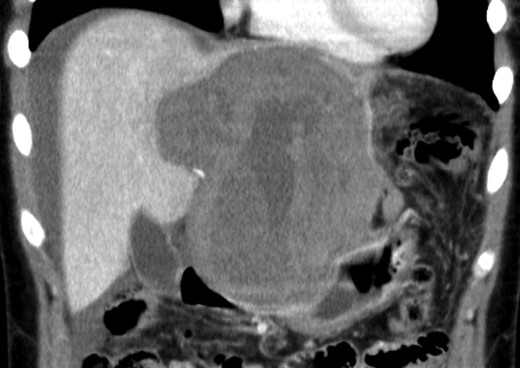

An 18-year-old woman presented with epigastric pain that started during a Japanese drum lesson. She was diagnosed with rupture of a hepatic tumor and transported to our hospital. She had no medical history of surgery, including abdominal surgery. Contrast-enhanced computed tomography (CT) revealed a 13-cm, low-density giant mass in the left hepatic lobe and high-density ascites, indicating abdominal bleeding from the liver tumor (Fig. 1). Ultrasonography confirmed a well-defined giant mass of the liver, comprising both cystic and solid lesions. Laboratory data showed a low hemoglobin level of 8.2 g/dl, and all the results of liver function tests and tumor marker measurement were within normal ranges. The patient underwent emergent celiac angiography, which revealed an avascular tumor with no evidence of extravasation from the hepatic artery. The left hepatic artery was considered to be the artery feeding the tumor and was embolized (Fig. 2). Magnetic resonance imaging (MRI) confirmed a well-defined giant multilocular lesion with fibrous partition (Fig. 3). After the patient's condition stabilized, she underwent left hepatic lobectomy. Laparotomy revealed bloody ascites and a large tumor in the left lobe of the liver; the right lobe appeared normal. The enlarged lymph nodes of the hepatoduodenal ligament were also dissected. Histological analysis of the resected specimen revealed a huge cystic mass of ∼12 × 9.5 cm. The mass was cystic and multilocular with a fibrous wall and filled with a massive blood clot (Fig. 4). The enlarged lymph node had a 25 × 23-mm cyst, which contained yellowish fluid. On microscopic examination, the wall of the cyst consisted of a tight elastic fiber meshwork composed of collagen fibers, which was accompanied by a small amount of acid mucopolysaccharide in the stroma and a lining of single-layered flat cells on the inner wall (Fig. 5a and b). Immunohistochemical staining revealed that the cyst wall was positive for both the endothelial marker CD31 and the lymphangial marker D2-40 (Fig. 5c and d). The cystic structure of the lymph node also was composed of elastic fiber components similar to those of the cyst in the liver and lined with single-layered flat cells, which were immunohistochemically positive both for CD31 and D2-40 (Fig. 5e). The pathological diagnosis was hepatic lymphangioma combined with lymphangioma of the lymph nodes. The patient's postoperative course was uneventful, and she was discharged on Day 8. During follow-up for almost 4 years since the surgical treatment, the patient has presented no sign of recurrence.

Emergent angiography demonstrated an avascular tumor and did not reveal any extravasation from the hepatic artery.